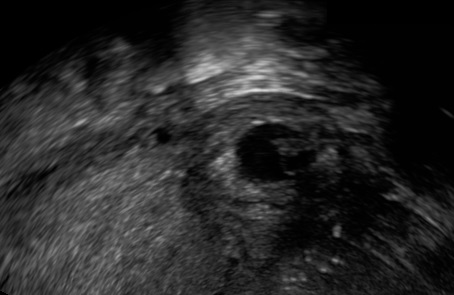

Visualize the ectopic pregnancy.